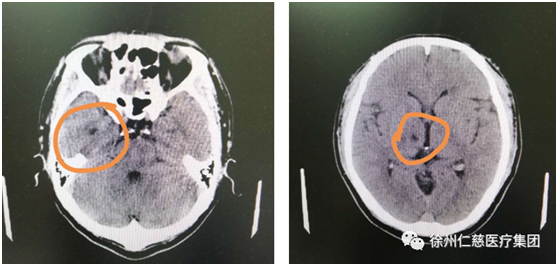

在徐主任的建議下,張師傅做了頭顱CT,檢查提示:兩基地節(jié)區(qū)、右側(cè)丘腦腔隙性腦梗塞,副鼻竇炎,腦干腔隙性梗塞不能排除。好在徐曉欣主任經(jīng)驗豐富,迅速聯(lián)系將張師傅轉(zhuǎn)入內(nèi)科,張師傅的腦梗得以及時治療。